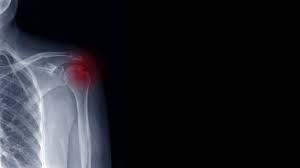

Schulter gebrochen ohne op. Der Bruch des Schlüsselbeins ist eine häufige Sportverletzung. Bestehen nach einem Unfall starke Schmerzen im Bereich der Schulter kann dies ein Hinweis auf eine Humeruskopffraktur sein. Eine Operation ist auch notwendig wenn die Schulter immer wieder ausrenkt.

Ob man sich die Schulter gebrochen hat wird man als Betroffener recht schnell bemerken da man starke Schmerzen in der Schulter hat und die Bewegungsfreiheit stark eingeschränkt ist. Arm und Schulter können nicht wie ursprünglich bewegt werden. Weiteres Anzeichen für einen solchen Bruch ist die Unfähigkeit den Arm oder die Schulter zu bewegen.

Ein Schulterbruch verursacht meist starke Schmerzen und Bewegungseinschränkungen. Folgende Komplikationen können im Zusammenhang mit der Operation entstehen. Der Bereich ist meist geschwollen und druckschmerzhaft.

Der Bruch des Schlüsselbeins ist eine häufige Sportverletzung. Ist es beim Unfall zu einer erheblichen Verschiebung der Knochenfragmente gekommen sind die Chancen auf ein gutes Ausheilen und Wiedergewinnen der Schulterfunktion ohne Operation schlecht. Während die Verletzung in der Vergangenheit fast ausschließlich konservativ also ohne Operation behandelt wurde erfolgt. Eine Schultersteife Frozen shoulder mit mehr oder weniger ausgeprägten Bewegungseinschränkung der Schulter und des betroffenen Armes ist mit und ohne Operation - manchmal zu beobachten. Auch das kann nur das MRT zeigen. Arm und Schulter können nicht wie ursprünglich bewegt werden. Implantat versagt bricht oder wandert. Etwa 85 Prozent der Brüche können ohne Operation behandelt werden. Nach Ruhigstellung von fünf bis sieben Tagen Dauer in einem speziellen Verband erfolgt die Übungsbehandlung zunächst noch ohne Belastung ab der siebenten Woche nach dem Unfall wird zunehmend belastet.

Weiteres Anzeichen für einen solchen Bruch ist die Unfähigkeit den Arm oder die Schulter zu bewegen. Eine Schultersteife Frozen shoulder mit mehr oder weniger ausgeprägten Bewegungseinschränkung der Schulter und des betroffenen Armes ist mit und ohne Operation - manchmal zu beobachten. Nach Ruhigstellung von fünf bis sieben Tagen Dauer in einem speziellen Verband erfolgt die Übungsbehandlung zunächst noch ohne Belastung ab der siebenten Woche nach dem Unfall wird zunehmend belastet. Der Bruch des Schlüsselbeins ist eine häufige Sportverletzung. Etwa 85 Prozent der Brüche können ohne Operation behandelt werden. Eine Operation geht immer mit gewissen Risiken einher wie zum Beispiel Entzündungen. Implantat versagt bricht oder wandert.